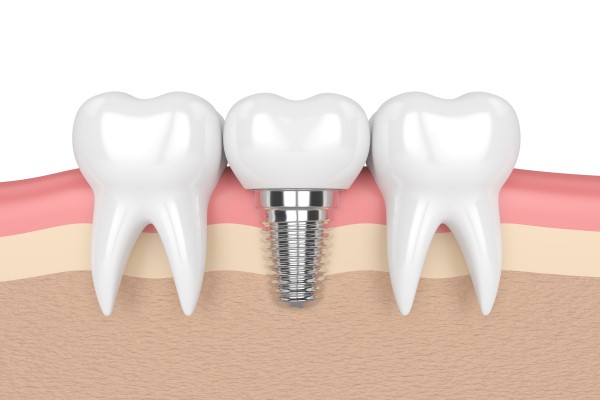

- Peri-Implantitis

- Peri-Implantitis refers to the inflammation of the soft and hard gum tissue that surrounds a dental implant and can be a result of losing supporting bone.